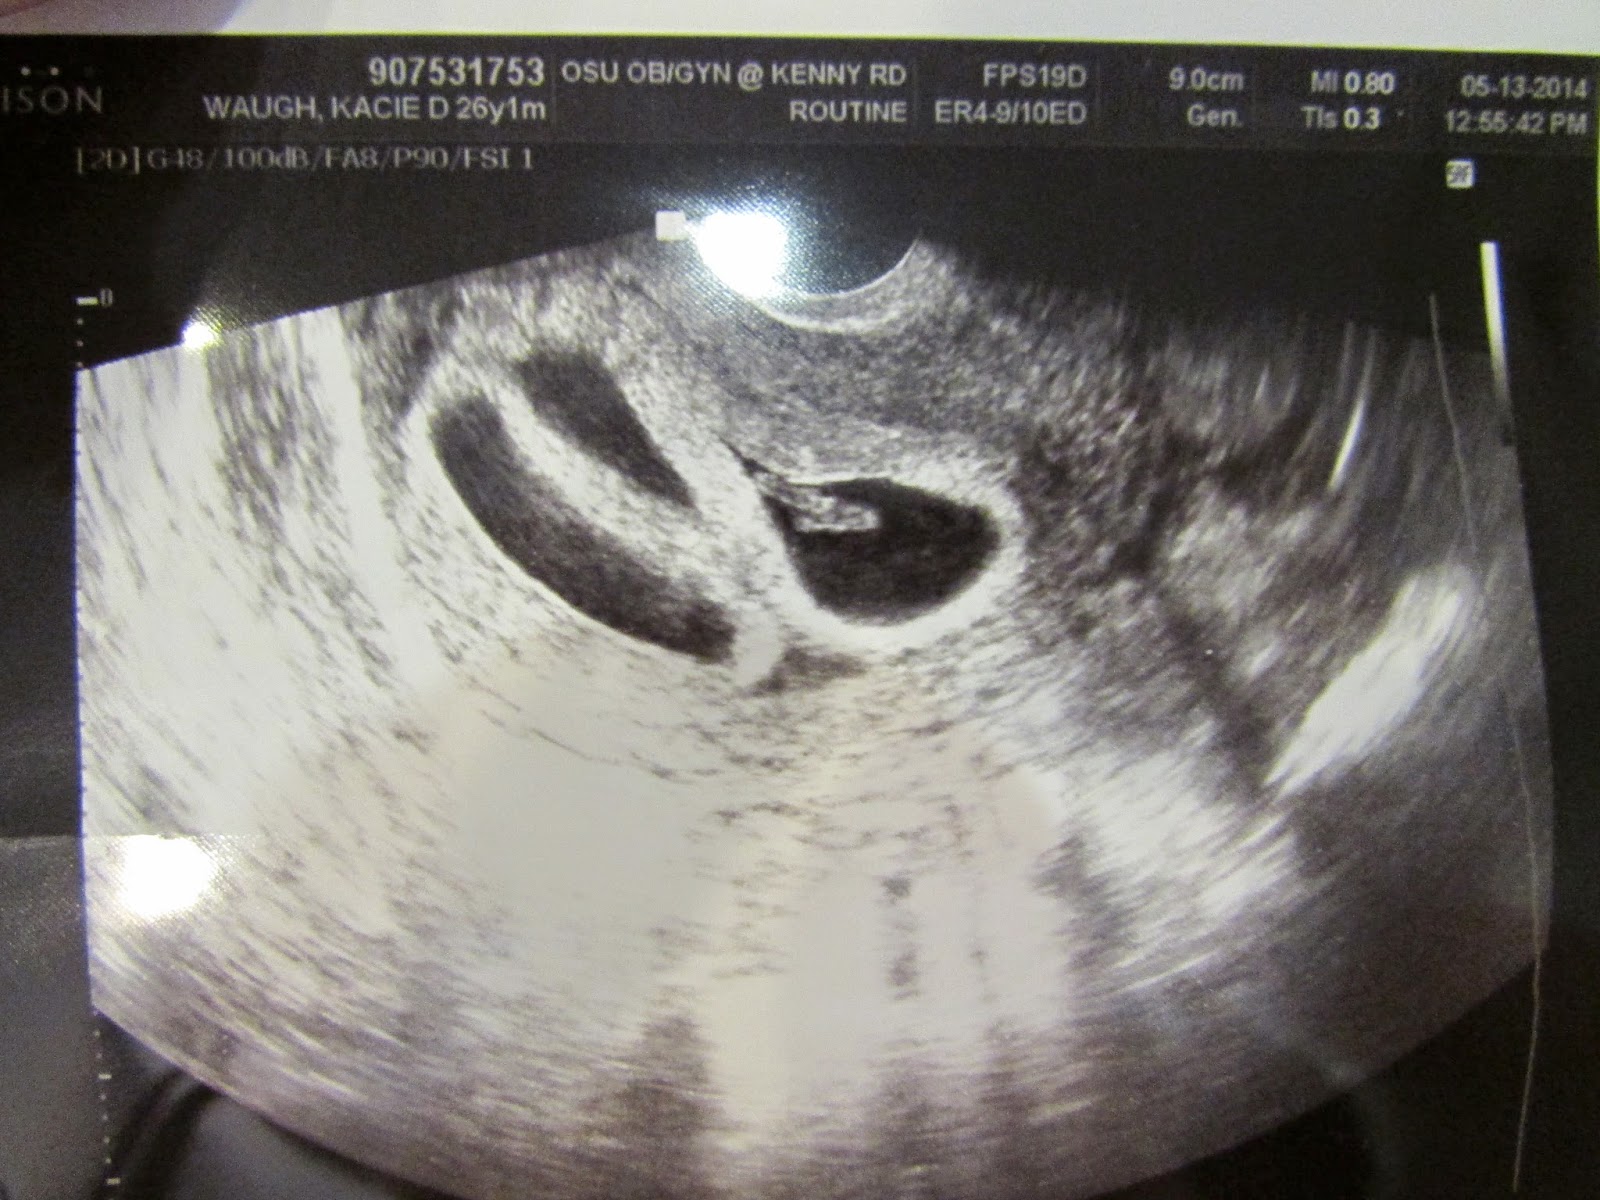

Well, Chris and I had a really important (at least it seemed that way to me) appointment with my high risk doctor this past Wednesday.  It was an important one for me because I had not been to see any doctor in 2 1/2 weeks (NOT doing that again), and they were also testing each of the babies for abnormalities.  Normally, this is a two-part test with an ultrasound and testing my blood, but with Quads, they cannot test my blood because if it came back positive, they would not be able to link it to any of the four babies individually.  So, my test was solely an ultrasound where they measured the size of this tiny little sac of fluid behind each baby's neck, checked to make sure each of them had nasal bones growing, and took a picture of the cross-section of each baby's head.  I was having a pretty rough week leading up to the appointment- lots and lots of stress and anxiety.  The morning of the appointment I went to get a manicure and pedicure to take my mind off of it all (not to mention it is getting harder and harder to reach my toes and they were in need of some serious TLC!).

Of course the entourage was with me for the appointment!  Chris, my mom Karla, and Chris' parents Dan and Lori all attended- good thing this place has big ultrasound rooms!  My mom again took a copious amount of notes- really helpful when I am writing these posts.  I love that Chris is always there because he is always a jokester and he puts my mind at ease!  I laid back, and the ultrasound tech went to work.  As soon as she came in I told her how very very nervous I was and she literally turned the machine on and within 5 seconds said, "I see four heartbeats!"  What a relief- we made it over the 12 week hurdle!  Then I looked up to the television screen that shows the ultrasound and I could not believe my eyes.  Those little tiny nuggets I had seen before (and that I shared with you all in my first post with the ultrasound pictures) were HUGE!  No wonder I am growing at such a rapid pace.

The ultrasound tech then went to work getting each of their measurements- no small feat.  We had to measure length, heart rate, the little fluid sacs behind each of their necks, the cross section of their heads, find the nasal bone, and then check the legs and arms of each one!  Not to mention that when measuring each of these things, they take the average of three measurements and each baby had to be laying a certain way without their typical gymnastics routine movements.  We were in for the long haul.  It actually ended up taking less time than expected or scheduled, and the babies each behaved perfectly!  It is a mother's touch, what can I say. =)

Well, let me get down to it.  They are all PERFECT!  Here are some highlights:

-Each baby is measuring at the size it should be or larger.  Again, great since they will be born so early!

-Each baby's fluid sac behind it's neck is measuring perfectly, and each has the nasal bones growing- important for the abnormality testing.

-All of the heart rates are within the normal range.

-Each baby is about 5.5cm long (around 2 inches).  It is amazing to me how much detail you can see even though they are "technically" still so small.

-Each baby (and especially baby C) likes to do gymnastics routines in my belly.  I can't imagine how this is going to feel once I start to actually feel their movements- can't wait!

-Each baby definitely has its own placenta!  This is something we were worried about for Baby B and Baby C, but we confirmed they are all separate on Wednesday which is very good news!  Also, this means there are no identical babies (actually, there are no twins at all).  So after trying for so long we successfully fertilized four separate eggs in one month.  Seriously, what are the odds?!  The doctor said less than the odds of getting struck by lightening randomly.  Can I get a lottery ticket over here?!